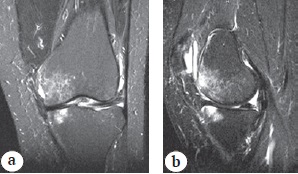

Patients of the main group (BMAC group) (n = 19) underwent a single intraosseous injection of BMAC in the area of bone marrow edema, whereas PRP (PRP group) was used in a similar procedure in the comparison group (n = 21). The zone of overload bone marrow edema and its localization were preliminarily determined according to MRI data and transposed to fluoroscopic images obtained during manipulations. Overload bone marrow edema was distinguished from aseptic necrosis by a change in the signal from the bone, which was characterized by low intensity on T1-weighted images and high intensity on T2-weighted images and short modes. Contrarily, the pathognomonic sign of aseptic necrosis was a line of low signal intensity along the periphery of the infarction focus with a bright inner line along the infarction surface on T1- and T2-weighted images. Foci of aseptic necrosis were predominantly located in the subchondral zone of the posterior-inner condyle parts of the femur and (or) tibia (Fig. 1, 2).

Fig. 2. Zone of overload edema of the femoral and tibial condyles in T1 mode: a — coronary section; b — sagittal section